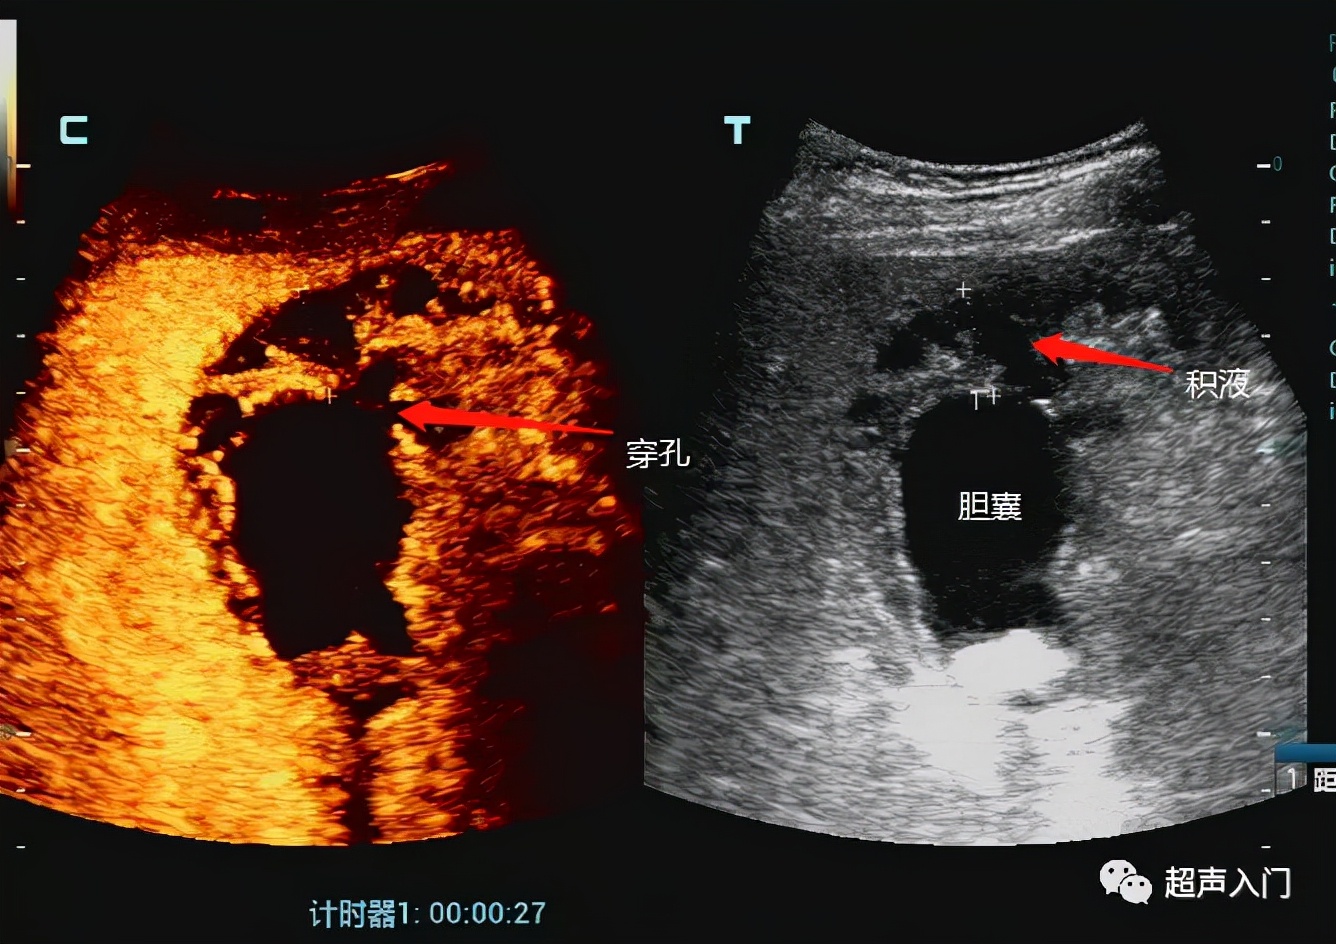

3、坏疽性胆囊炎,胆囊极度肿大,如胆囊壁血液循环发生障碍时该处可发生出血坏死,甚至穿孔而并发局限性或弥漫性腹膜炎。若有产气杆菌感染,胆囊内可积气,但较少见,好发于老年及糖尿病患者。

6、急性胆囊炎穿孔时,可显示胆囊壁的局部膨出或缺损,以及胆囊周围的限局性积液。